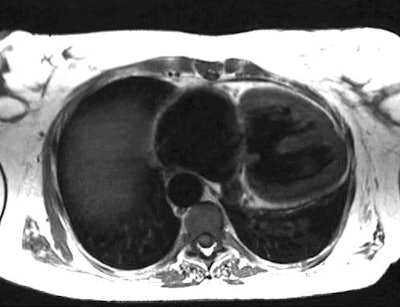

MRI of a Muscular VSD:

Submitted by Dr. Scott Flamm, M.D.

The lesion demonstrated is a muscular VSD in an adult patient. We know that this is a muscular VSD and not a membranous lesion because the image was obtained low in the septum. This is apparent because we are seeing the right atrium and almost no left atrium (remember- the left atrium sits higher than the right atrium). A membranous VSD would be higher by about 3-4 cm (in an adult).